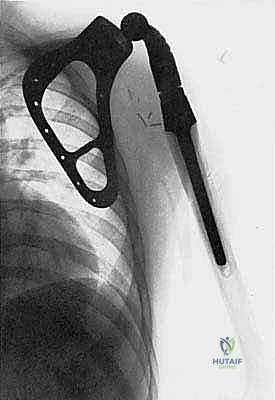

- أورام الكتف: يتم استئصال أعلى عظم العضد وربما جزء من لوح الكتف، واستخدام مفصل كتف صناعي. الهدف هنا هو الحفاظ على وظيفة اليد والكوع بشكل كامل، مع توفير استقرار للكتف.